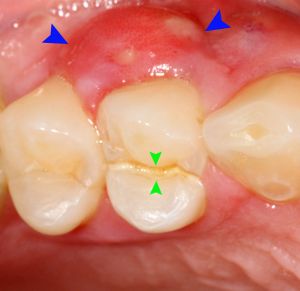

Tályog a szájban – képek

A tályog a szájban képek forrása a Wikipédia.